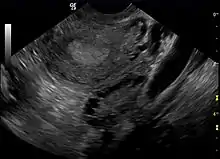

A constatação, através de exame de ultrassom, de que os ovários apresentam múltiplos cistos foi por muito tempo considerada a característica patognomônica para o diagnóstico da SOP, mas parece ser um achado inespecífico em aproximadamente 20% das mulheres que são assintomáticas[111]. Atualmente, considera-se o fato de apresentar ovários policísticos por si só insuficiente para diagnosticar síndrome. Também a inexistência de cistos ovarianos não descaracteriza, necessariamente, a ocorrência da síndrome[112][8]. Asso, nem todas as pacientes com SOP apresentam ovários policísticos e, da mesma forma, nem todas as mulheres com cistos ovarianos podem ser automaticamente diagnosticadas como portadoras da síndrome. Embora o exame de ultrassonografia pélvica seja uma importante ferramenta de diagnóstico, ela não é a única.[113]

Ultrassonografia ginecológica especificamente voltada para a localização de pequenos folículos ovarianos. Estes são acreditados como resultado da função ovariana perturbada com a ovulação falha, refletida pela menstruação infrequente ou ausente, sendo esta uma manifestação típica da doença. Em um ciclo menstrual normal, um óvulo é liberado do folículo dominante - em essência, um cisto que se rompe para liberar o óvulo. Após a ovulação, o remanescente do folículo é transformado em um corpo lúteo produtor de progesterona, que encolhe e desaparece após cerca de 12-14 dias. Na SOP, há uma assim chamada "prisão folicular", isto é, vários folículos desenvolvem-se até um determinado tamanho (geralmente entre 5-7 mm), mas não mais do que isso. Nenhum folículo atinge o tamanho pré-ovulatório (16 mm ou mais). De acordo com os critérios de Rotterdam, ao menos 12 ou mais folículos pequenos devem ser encontrados no ovário durante o exame de ultrassom.[78] Os folículos podem ser orientados na periferia, dando a aparência de uma "cadeia de pérolas". Os inúmeros folículos contribuem para o aumento do tamanho dos ovários, ou seja, cerca de 1,5 a 3 vezes maior do que o normal.

A síndrome adquiriu seu nome mais amplamente utilizado devido ao sinal comum no exame de ultrassom de múltiplos (poli) cistos ovarianos. Estes "cistos" são na verdade folículos imaturos, não cistos. Os folículos se desenvolveram a partir de folículos primordiais, mas o desenvolvimento foi interrompido ("preso") numa fase antral precoce devido à perturbação na função ovariana. Os folículos podem ser orientados ao longo da periferia do ovário, aparecendo como um "colar de pérolas" no exame de ultrassom.